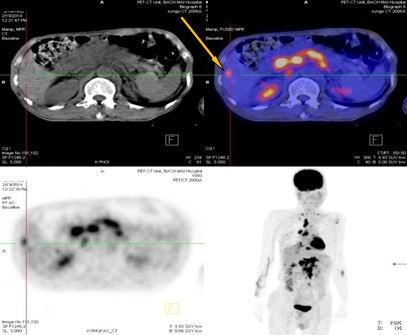

+ Nhiều hạch ổ bụng dọc theo ĐM chủ bụng tạo thành khối lớn KT 8,5x5,1 cm và 5,1x3,9cm, tăng hấp thu F-18 FDG, max SUV=10,45. Nhu mô gan hạ phân thùy VI có nốt KT 1,2cm, tăng hấp thu F-18 FDG, max SUV=4,15.

-Trước điều trị: Nhiều hạch ổ bụng dọc theo ĐM chủ bụng tạo thành khối lớn KT 8,5x5,1 cm và 5,1x3,9cm,  max SUV=10,45.

-Sau điều trị 4 tháng: Không có hạch ổ bụng

Trước điều trị: Hạ phân thùy VI gan P có nốt 1,2cm, max SUV= 4,15. Hạch ổ bụng: 8,5x5,1 cm  max SUV=10,45

Sau điều trị 4 tháng: Không có tổn thương